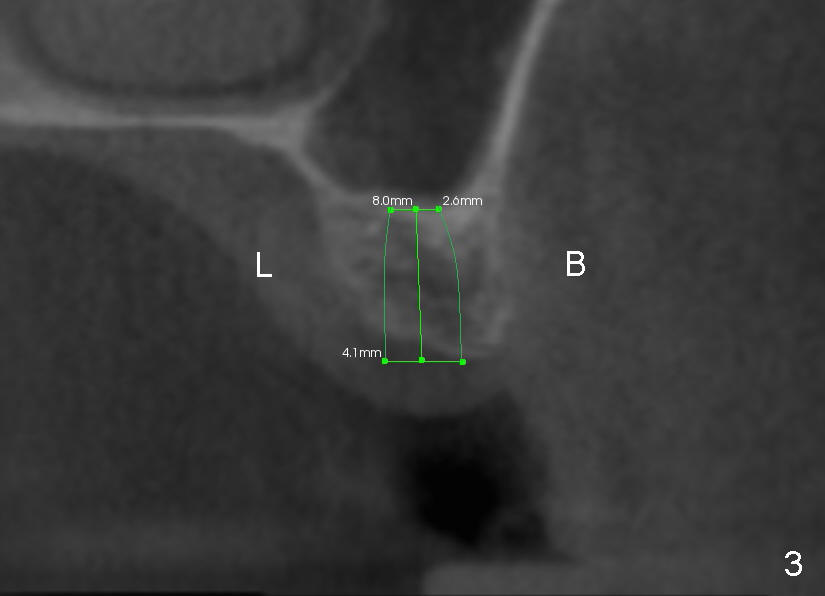

A 44-year-old lady has lost two of the 1st molars (upper left (Fig.1-3) and lower right (Fig.4-6)) for several years. Fig.1,4 are preop PAs, Fig.2,5 CT sagittal sections, and Fig.3,6 CT coronal sections. The adjacent teeth shift and tilt into the edentulous space.